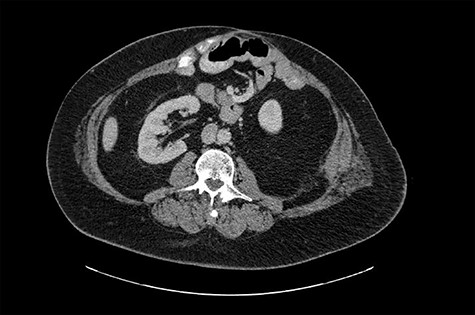

Laboratory values showed evidence of an acute kidney injury with suggestive urinary tract infection. Renal ultrasound demonstrated bilateral nephrolithiasis with moderate left hydronephrosis. Abdominal/pelvic CT scan confirmed left proximal ureteral stone with left hydronephrosis and a prominent parastomal hernia at the ileostomy site, which contained portions of the right kidney, right proximal ureter, mesenteric/retroperitoneal fat and some bowel (Fig. 2).

CT image from 2019 shows a prominent (2.3 cm ML) ventral hernia at the ostomy site, including portions of mesenteric/retroperitoneal fat, portion of right kidney, right proximal ureter and some bowel.